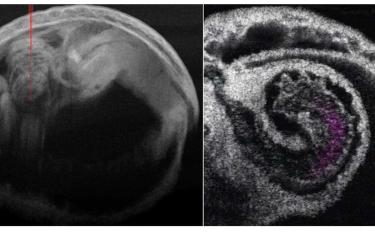

Investigadores del Instituto de Tecnología Stevens e Irina Larina del Colegio de Medicina Baylor (Estados Unidos) han utilizado por primera vez la tomografía de coherencia óptica (TCO) en 4D para estudiar el mecanismo de bombeo subyacente al corazón de los mamíferos en desarrollo. Su informe, publicado en la revista 'Journal of Biomedical Optics', demuestra que la imagen de TCO en 4D del corazón embrionario de un ratón puede proporcionar información sin precedentes sobre cómo funciona el corazón temprano de un mamífero.

Las escalas de imagen únicas y los contrastes dinámicos que ofrece la TCO permiten una profundidad de imagen a nivel milimétrico con una resolución a microescala para capturar todo el corazón del ratón en las etapas medias de la gestación. La TCO también proporciona una visión clara de las finas estructuras cardíacas así como del flujo sanguíneo. La alta velocidad de imagen de la TCO junto con la sincronización post-adquisición permite reconstruir la rápida dinámica del corazón que late.

Aunque tradicionalmente se ha pensado que el mecanismo que bombea la sangre dentro del tubo cardíaco embrionario son las contracciones peristálticas ondulantes, los investigadores pudieron ofrecer una evaluación más detallada utilizando la TCO 4D para integrar la cardiodinámica y la hemodinámica. Sus observaciones piloto sugieren que el bombeo localizado del tubo cardíaco en los ventrículos funciona a través de una combinación de mecanismos de succión y empuje.